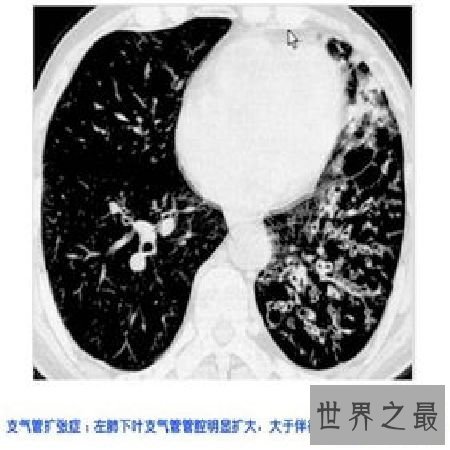

支气管扩张是指因为支气管及其周围组织的慢性炎症和气道阻塞,导致支气管的组织构造遭到较重大的病感性破坏,惹起管腔扩张和变形的支气管慢性疾病。一支或多支近端支气管和中等大小支气管管壁组织破坏形成不可逆性扩张。